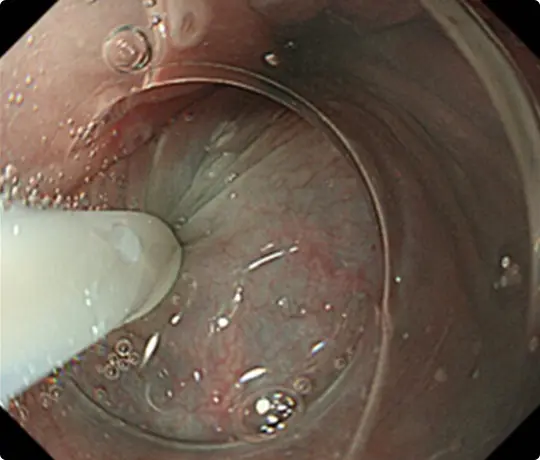

生理食塩水の中で行うESDです。水中では光の反射による視野障害がなくなり、自然な拡大効果もかかるため、鮮明な視野が得られます。

ケースバイケースで従来のESDと使い分けています。

この方法は2018年に当科が原著形式の英語論文として発表し、消化器内視鏡のトップジャーナルであるGastrointestinal Endoscopy(GIE)に掲載されました。

全国的にもまだ出来る病院が少ない十二指腸ESDを提示します。十二指腸ESDではUnderwater ESD(生理食塩水の中で行うESD)が有効です。

約25mmの十二指腸腫瘍を認めます。

Underwater ESD(生理食塩水の中で行うESD)を行うことで光の反射がなくなり、拡大効果もあるため、精密に剥離することが可能になります。

当科で考案したUnderwater ESD(生理食塩水の中で行うESD)を行うことで光の反射がなくなり、拡大効果もあるため、鮮明な視野が得られ粘膜下層と筋層の境界が分かりやすくなります。筋層を傷つけないように、精密に剥離することが可能になります。